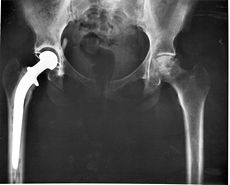

The idea was to assemble a sculpture out of donated hip bones (femur heads) obtained from consenting, living patients undergoing so-called hip replacement surgery in a hospital in London. Patients may be undergoing partial or total hip replacement ie total hip arthroplasty. The femur head is the ball that fits in the socket; about the size of a golf ball. If you think about it, the human skeletal system is a mind boggling design:- built to withstand 80 years plus of wear and tear, generally self repairs and grows in size from babe in womb to full adult. Now if we had a car with a chassis that could last that long, self repair and expand from dinky toy dimensions to the full model then one might properly term that as ‘awesome’.

For me this art project was reflection of the processes in my own science research work; lot of dead ends, circles, processes, and re-starts. The resulting sculpture has been discussed by Gina in her blog and book ‘Humancraft’; some, no doubt, nuanced many layered concepts relating to Liverpool, the British Empire, preservation and permissions about our bodies. But when I see this sculpture I see the wheel and femur heads; to me it’s a mobility mobile, a reflection of the donors who are increasingly in pain (evidence the wear marks on the femur head) waiting, incapacitated, desiring to stay mobile and independent with their dignity intact. The choice of the wheelchair or literally running free. Elderly citizens [that will be you one day if you are lucky]; is the choice simply preservation or an attempt to give a quality life for as long as possible? This brings us back to the increasing choices that we will face about how we view our bodies and the extent to which we can intervene/modify and upgrade.